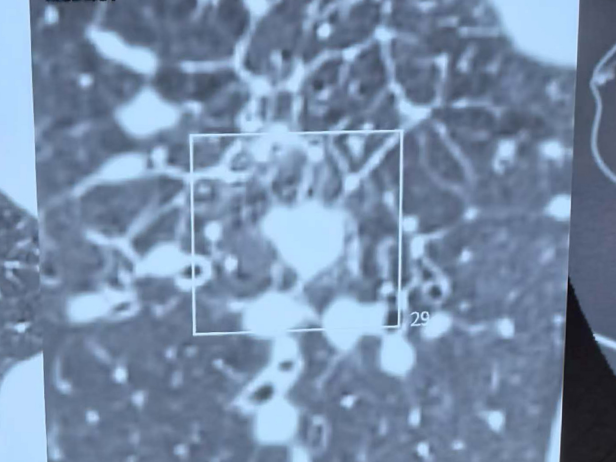

禁区操作精准消融突破困境

在麻醉团队的全力保障下,陶冀教授团队凭借丰富的临床经验和精湛的技术,采取左侧卧位,运用单针精准分段穿刺技术,如同一位技艺高超的工匠,将消融针尖精准无误地置入病灶核心。术中,他们以30—40W的中低功率进行消融,持续9分钟后,谨慎退针并补充消融,通过两个精心设计的消融循环,确保消融范围完全覆盖病灶,实现肿瘤的彻底灭活。手术过程顺利,术中无出血,仅出现少量气胸,经置管抽气后迅速缓解,重要血管与支气管均得到妥善保护。